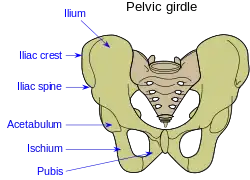

Pelvic girdle. | |

The crest of the ilium (or iliac crest) is the superior border of the wing of ilium and the superiolateral margin of the greater pelvis.

The iliac crest stretches posteriorly from the anterior superior iliac spine (ASIS) to the posterior superior iliac spine (PSIS). Behind the ASIS, it divides into an outer and inner lip separated by the intermediate zone. The outer lip bulges laterally into the iliac tubercle.[1] Palpable in its entire length, the crest is convex superiorly but is sinuously curved, being concave inward in front, concave outward behind.[2]